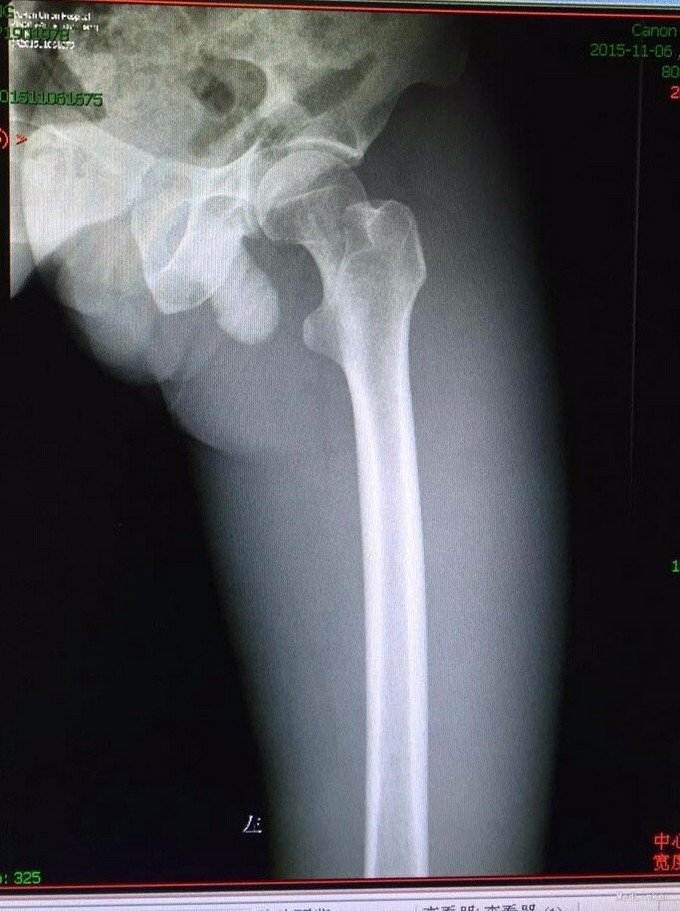

患者男,45岁,因“左髋部摔伤五日余”入院。 患者自诉于五日前步行时不慎摔伤,左髋部着地,伴疼痛,活动受限,遂求治于当地医院,行影像学检查示:左侧股骨颈骨折,给予止痛制动及其他对症支持治疗,治疗后症状无明显好转,遂转入我院,门诊以“左侧股骨颈骨折”收入院。 患者摔伤以来,精神睡眠饮食可,大小便正常,体力一般,体重无明显下降。 既往患者心衰史十余年,新功能三级,口服阿伐他丁、培哚普利、阿司匹林、螺内酯、速尿等控制病情;十年前行瓣膜置换术。其余无特殊。

查体:T:36,2℃,P:86次/分,R:20次/分,BP:135/80mmHg。神志清楚,查体合作,面容正常,全身浅表淋巴结无肿大。心肺腹无异常,双下肢无水肿。生理反射存在,病理反射未引出。 专科情况:患者卧床,不能行走,脊柱生理弯曲存在,未及明显畸形,双上肢皮肤感觉运动可,右下肢皮肤感觉运动可,右髋压痛阴性,右膝压痛阴性,直腿抬高试验90度,四字征阴性,左下肢外旋畸形,较右下肢稍缩短,皮肤感觉可,左髋压痛阳性,左膝压痛阴性,直腿抬高试验及4字征因疼痛不能配合,双侧膝跳反射正常,巴氏征阴性,余生理反射存在,病理反射未引出。 辅检:外院影像学检查是:左股骨颈骨折。我院术前检查无异常,影像学检查见下图。

诊断:左大腿血肿,皮下水肿;心力衰竭(心功能3级) 治疗:止血、脱水、抗心衰、其他对症支持治疗。

这个病人应该是下面医院诊断错了,患者并没有骨折,在我院行止血,脱水等一般治疗。骨折的特有体征有畸形、异常活动、骨擦音或骨擦感,以上三种体征只要发现其中之一,即可确诊。临床症状和体征外,更有影像学检查结果可以确诊,所以骨折的确诊还是比较清楚容易的。